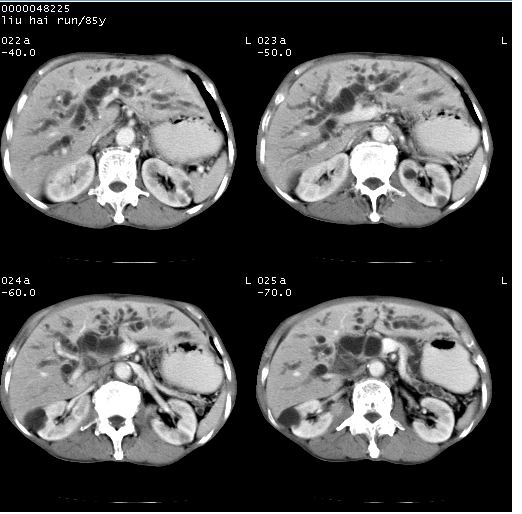

标题: CT13403:M,85Y。胆系低位梗阻。胰头占位? [打印本页]

标题: CT13403:M,85Y。胆系低位梗阻。胰头占位?

彩超示胰头实质欠均匀,胰管扩张。

影像表现:壶腹部扩张胆管呈截断样改变,肝内外胆管重度扩张,胆囊增大,胰管亦明显扩张,呈不规则患珠样,胰体尾部略有萎缩,增强扫描后壶腹部低密度影轻度强化,与钩突分界不清。

ct诊断:胆管癌。鉴别诊断:胰腺癌,胰腺癌为少血供肿瘤,增强后强化不明显,静脉期及延时后与正常胰腺分界清晰。

1)胆系低位梗阻(肝内外胆管扩张、胰管扩张、胆囊增大);考虑为:胰头癌可能性大,不排除胆总管下端癌。2)双肾多发囊肿。